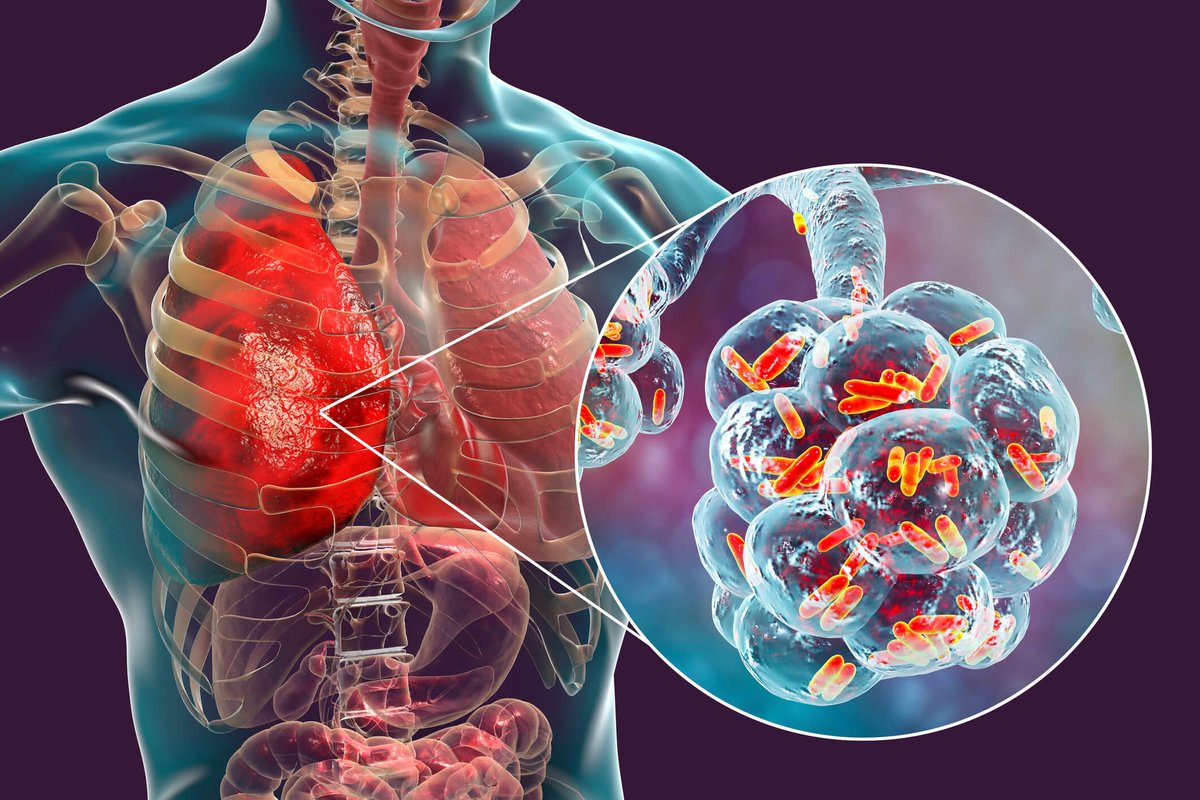

Бактерии и вирусы в легких

Пневмония - это серьезное заболевание легких, которое может быть вызвано различными причинами, включая бактериальные, вирусные и грибковые инфекции. Для того чтобы наглядно показать симптомы, диагностику и лечение этого заболевания, картинки могут быть очень полезны.

Картинки с симптомами пневмонии

В этом разделе представлены изображения, демонстрирующие различные симптомы пневмонии, такие как кашель, одышка, боль в груди и повышенная температура. Эти картинки могут быть использованы для обучения и презентаций в области медицины и здравоохранения.